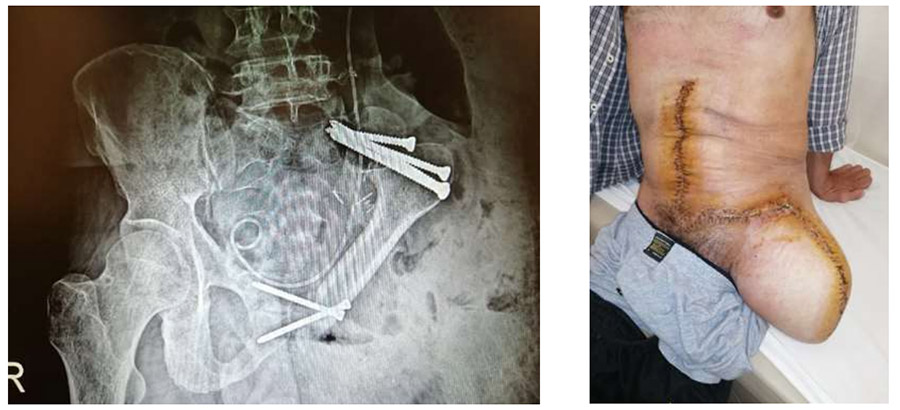

Ameliyat Sonrası: Röntgende proksimal femur ile yapılan rekonstrüksiyon ve yaranın klinik görüntüsü görülmekte